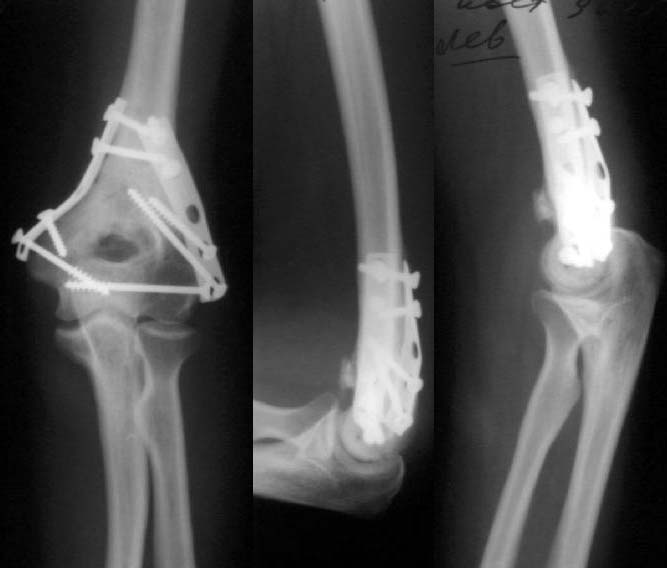

До лечения

Результат в 6 месяцев

Лечение тут, видимо, должно основываться в первую очередь на открытой репозиции, поскольку возможности закрытой при таких повреждениях далеко недостаточны. Если поверхность блока состоит не просто из двух крупных фрагментов, лучше идти с отсечением локтевого отростка. Вопрос о методе фиксации более второстепенный. Можно и аппаратом. В приложении - пример лечения такого повреждения с внутренней фиксацией.